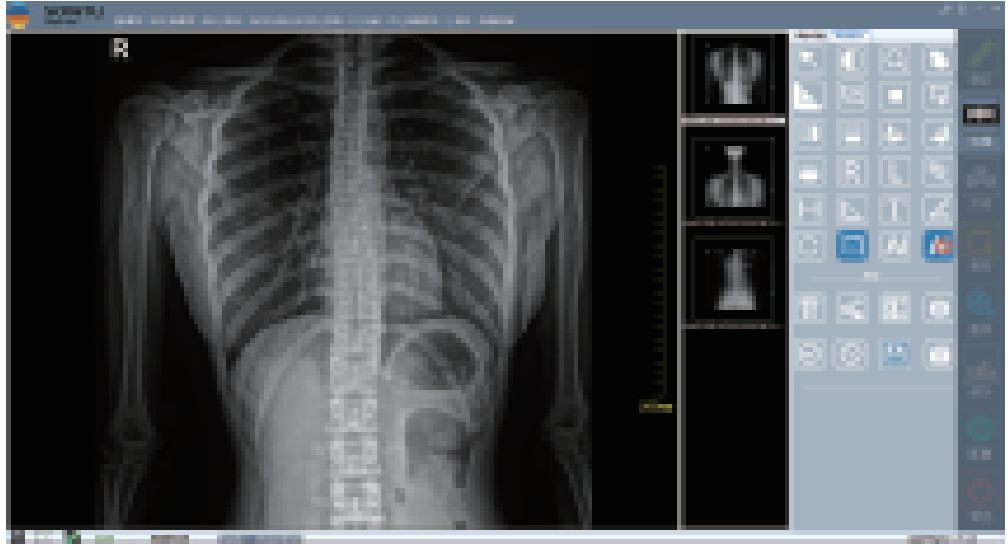

图像采集

图像操作

登记

保存

打印